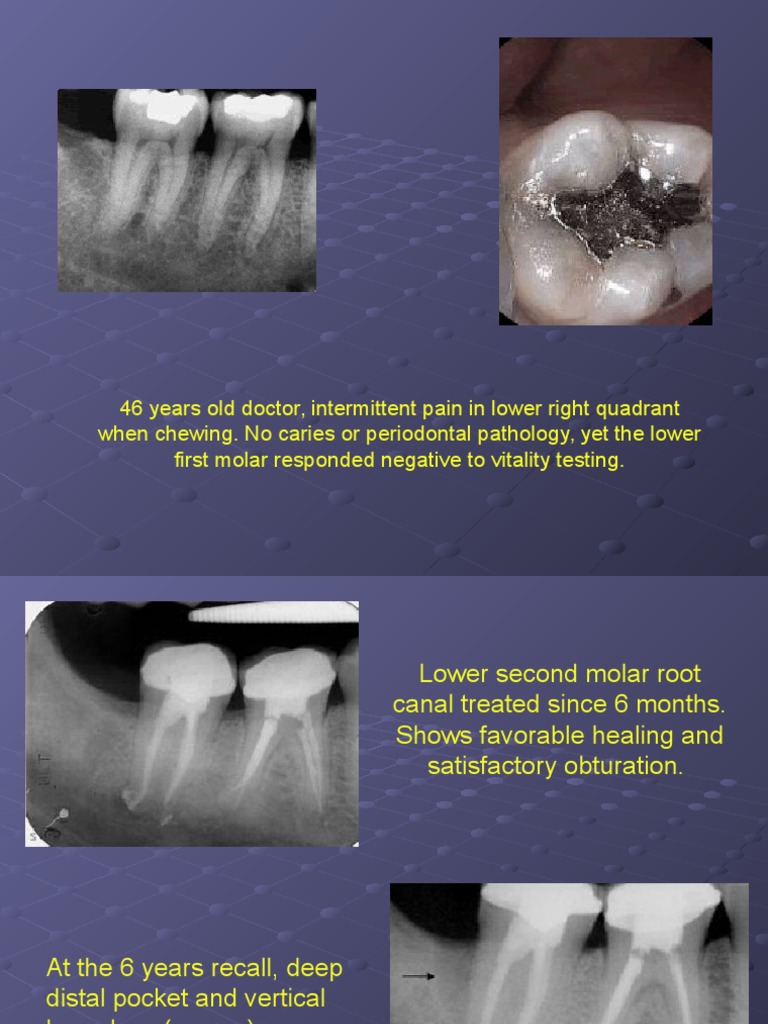

Cracked Tooth Syndrome - Style Italiano Endodontics

Cracked tooth syndrome - Style Italiano Endodontics endodontics.styleitaliano.org

Cracked tooth syndrome - Style Italiano Endodontics